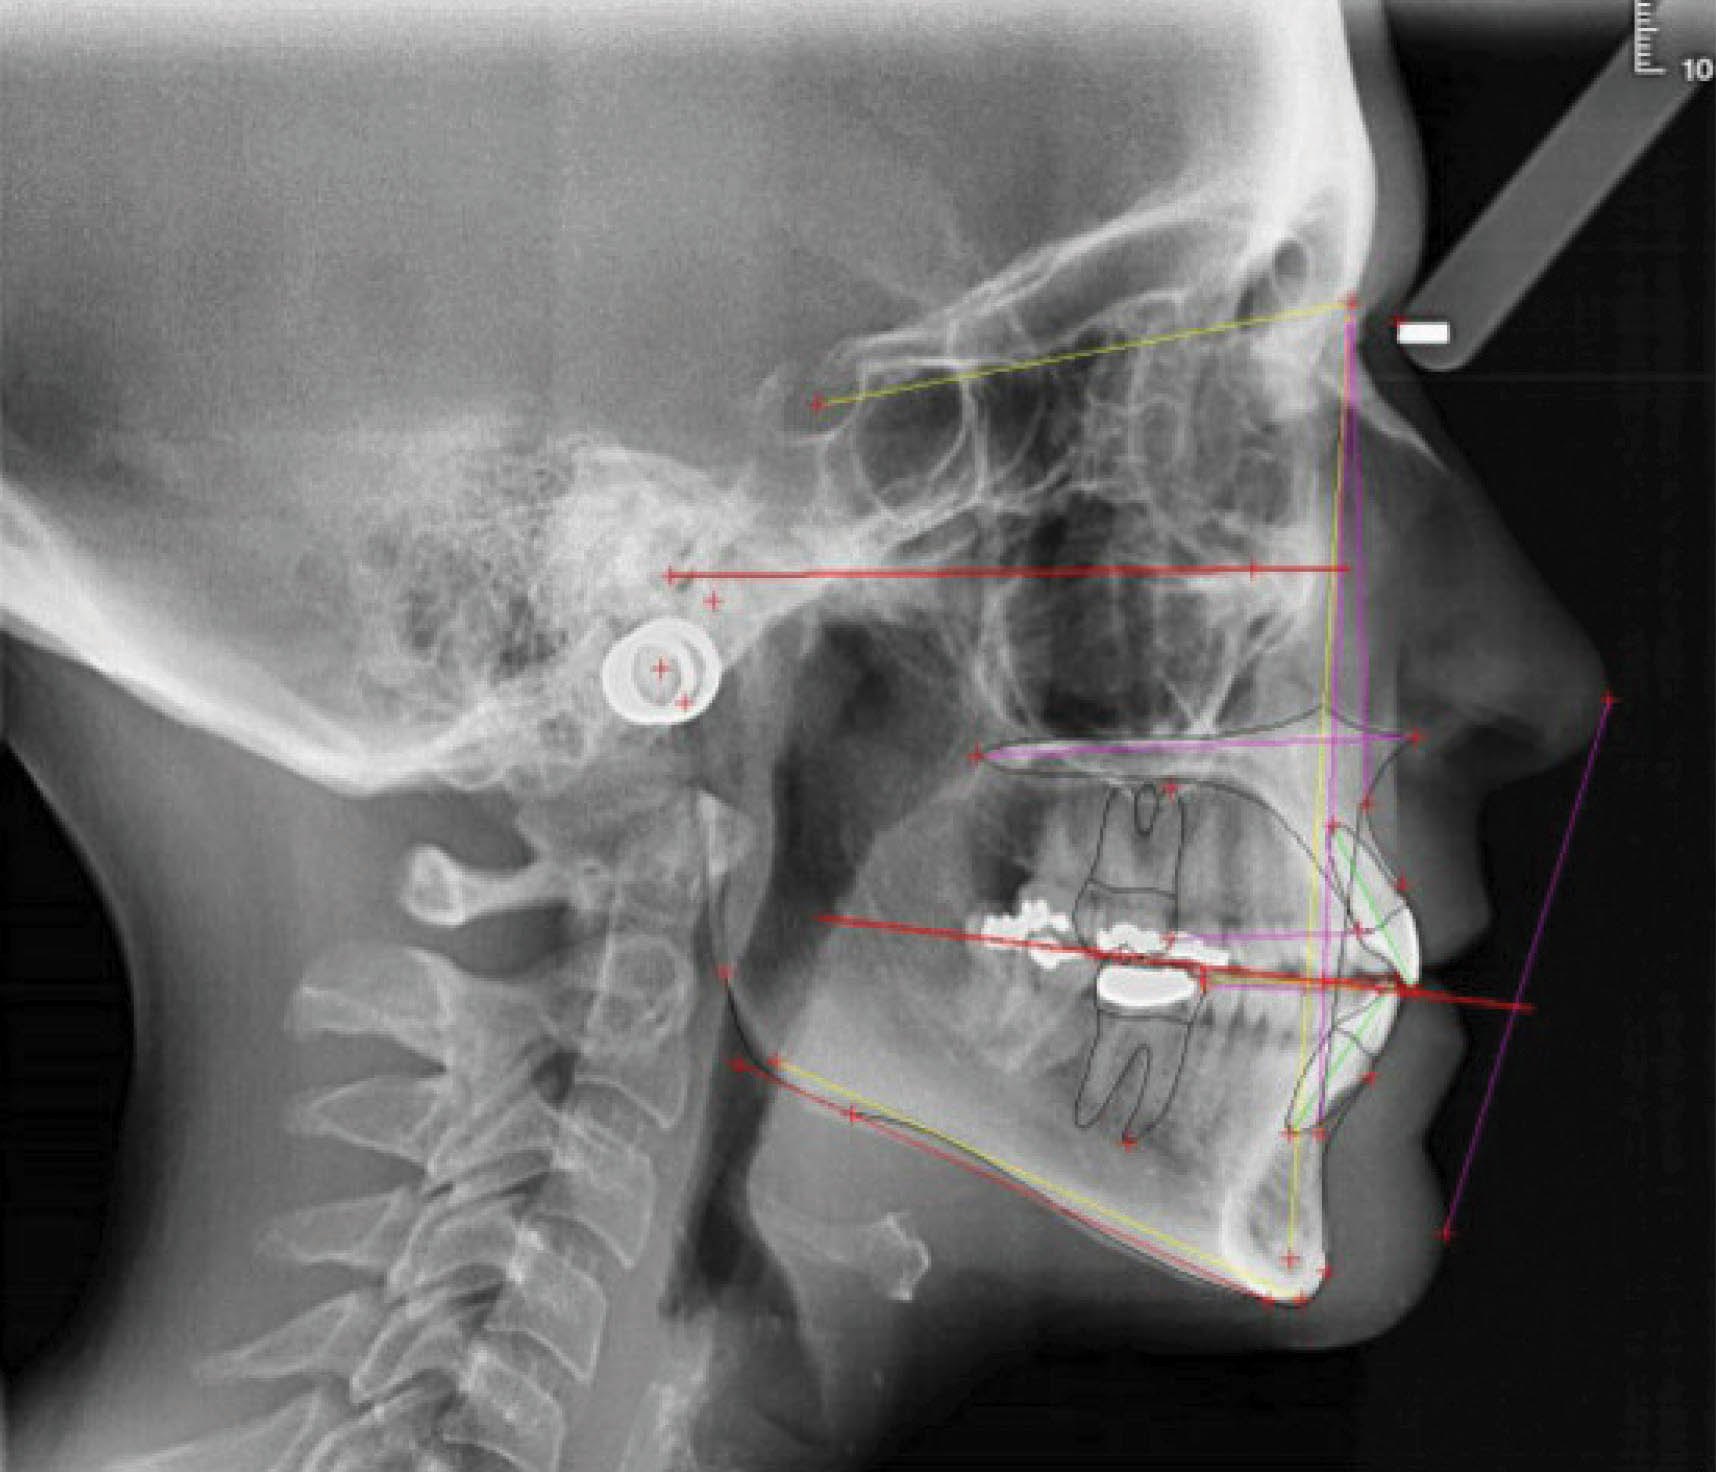

بیمارClII/2 با دیپ بایت شدید و ارتفاع عمودی کم صورت است (شکلهای 73-6 الی 75-6).

شکل 73-6

شکل 74-6

شکل 75-6

در چک لیست درمان مشاهده میکنید که انسیزورهای رترود شده بالا نیاز به اینتروژن نسبی (به کمک پروترود شدن) دارند، در حالیکه انسیزورهای پایین نیاز به اینترود شدن مطلق دارند تا کرو اسپی صاف بشود. علاوه بر این، نیاز به اکستروژن خلف هم داریم تا ارتفاع عمودی صورت بیشتر گردد. از بایت پلیتهای قدامی برای حذف نیروهای اکلوزالی (که مانع اصلاح دیپ بایت و اکستروژن خلف است) استفاده نمودیم.

میزان نمایش لبه انسیزال میزان نمایش لثه مارجین لثه قوس لبخند

دیپ بایت: اینتروژن قدام بالا پایین اکستروژن خلف بالا پایین

اپن بایت: اکستروژن قدام بالا پایین اینتروژن خلف بالا پایین

اکستروژن یا اینتروژن نسبی انسیزور های بالا مطلق انسیزور های های پایین